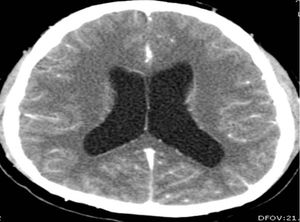

신경낭미충증 MRI

뇌 내에 다수의 낭미충을 보여주는 신경낭미충증 환자의 자기 공명 영상

CT와 MRI는 병변의 수, 양상, 치유 단계, 면역계의 기생충 반응에 대한 객관적인 정보를 제공한다.[7] MRI는 다양한 각도에서 평가가 가능하고 선명한 영상을 제공하여 CT 스캔에서 놓칠 수 있는 뇌 뒤쪽이나 두개골 근처의 작은 병변을 식별하는 데 유용하다. CT는 뇌의 석회화를 감지하는 능력이 뛰어나 뇌의 칼슘 축적을 확인하는 데 더 민감하다.[2]

살아있는 소포성 낭종은 작고 둥근 병변으로, 주변 부기가 거의 없고 조영제가 필요하지 않다. 촌충 머리(스콜렉스)는 보통 낭종 내부에 비대칭적인 결절로 나타나며, 이러한 머리를 가진 여러 개의 살아있는 낭종은 진단을 뒷받침한다. 낭종이 파괴되기 시작하면(콜로이드 낭종) 경계가 불분명해지고 부기로 둘러싸이며, 링 또는 결절성 조영 증강을 보인다. 석회화된 유구낭미충은 CT 스캔에서 부기 없이 조영되지 않는 고밀도 결절로 나타난다.[8]